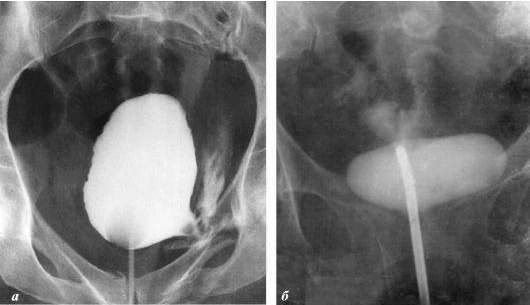

+ Vedere le immagini (18+)

interesting image

Cancro alla prostata in un uomo di 58 anni.